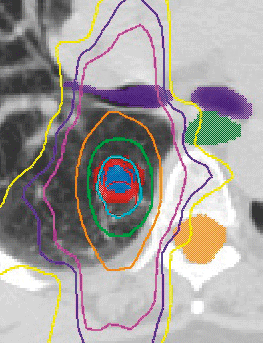

• CT-based treatment planning: On-site CT interfaces with the treatment planning system, allowing the radiation oncologist to customize a treatment plan for each patient. With the use of sophisticated software, the physician can view the radiation dose 3-dimensionally, maximizing the cancer-killing radiation to the tumor while minimizing radiation to other areas of the body.

• We offer Volumetric modulated arc therapy (VMAT), a novel radiation therapy technique that delivers the radiation dose continuously as the treatment machine rotates. This technique accurately shapes the radiation dose to the tumor while minimizing the dose to the organs surrounding the tumor in less time than IMRT.